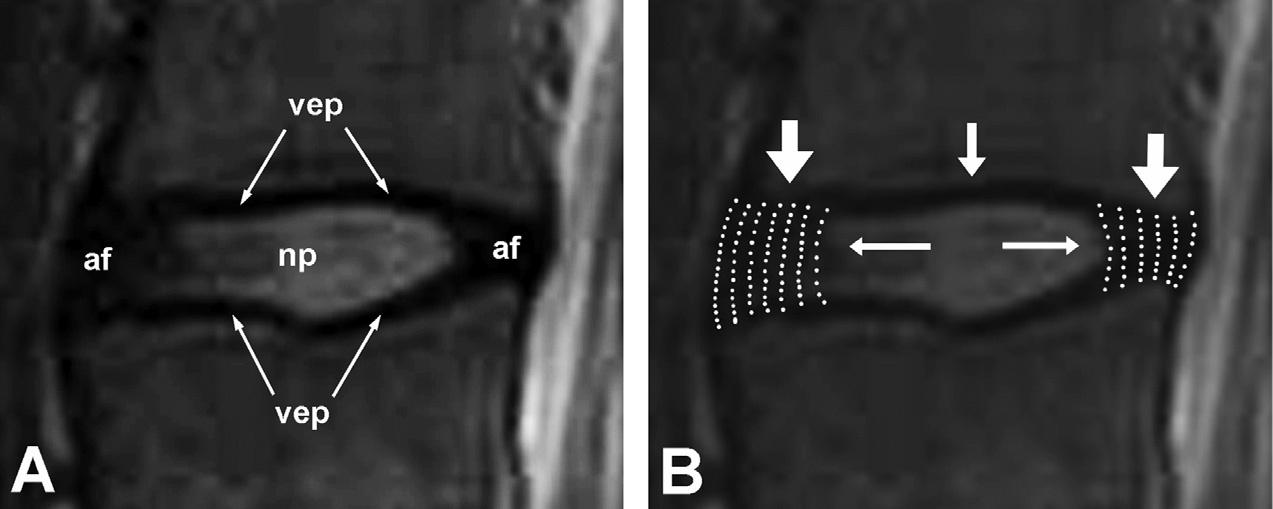

Fig.32.12. Close-upviewsofasagittalmagneticresonanceimageofanL3–4intervertebraldisc.(A)Thecomponentsofthedisc. np,nucleuspulposus;af,anulusfibrosus;vep,vertebralendplate.(B)Themechanicsofthedisc.Axialcompressionloadsare primarilybornebythelamellaeofcollagenintheanulusfibrosus.Whencompressed,thenucleuspulposusexertsradialpressure tobracetheanulus,andpreventitfrombucklingunderload.